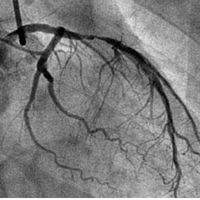

- 冠状动脉造影编辑锁定本词条由好大夫在线提供内容并参与编辑,袁晋青,主任医师,阜外心血管病医院冠心病诊治中心陈珏,主任医师,阜外心血管病医院冠心病诊治中心谭晓燕,副主任医师,阜外心血管病医院冠心病诊治中心冠状动脉造影是诊断冠状动脉粥样硬化性心